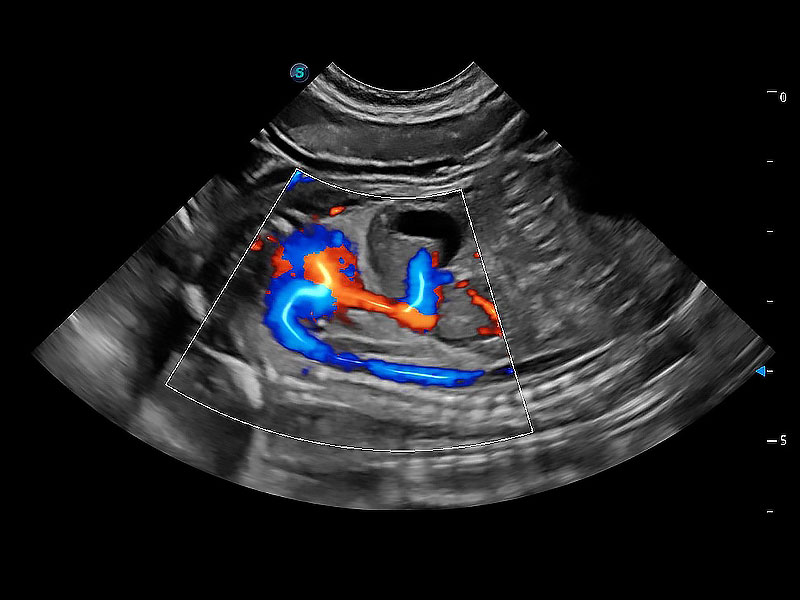

(犬)二腔心血流

• Bright Flow 立体血流成像

在传统二维血流成像的基础上,呈现血流的立体感,具有动感的生命力之美。即便是微小的血管也能轻松应对,提高了血流的视觉敏感性。